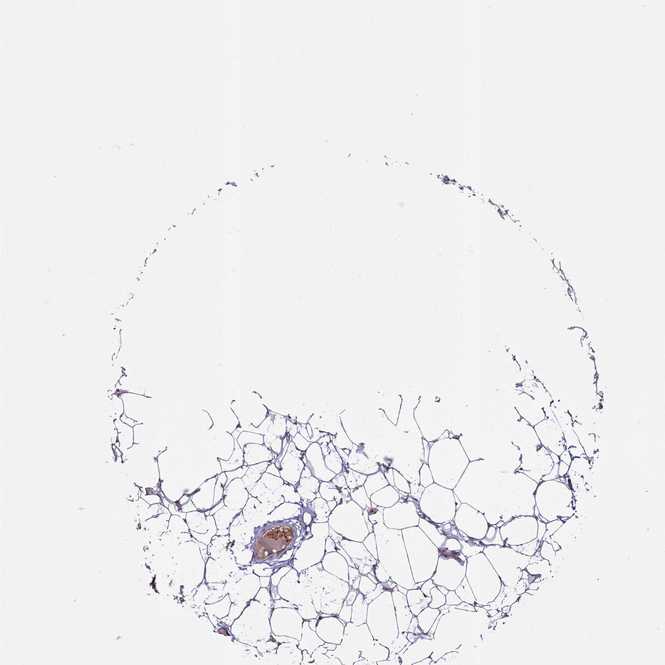

ADIPOSE TISSUE - Antibody stainingi

Antibody staining in the annotated cell types in the current human tissue is reported as not detected, low, medium, or high, based on conventional immunohistochemistry profiling in selected tissues. This score is based on the combination of the staining intensity and fraction of stained cells.

Each image is clickable and will lead to virtual microscopy that enables deeper exploration of all samples and also displays staining intensity scores, fraction scores and subcellular localization as well as patient and tissue information for each sample.

Antibody HPA017963

Adipocytes Low